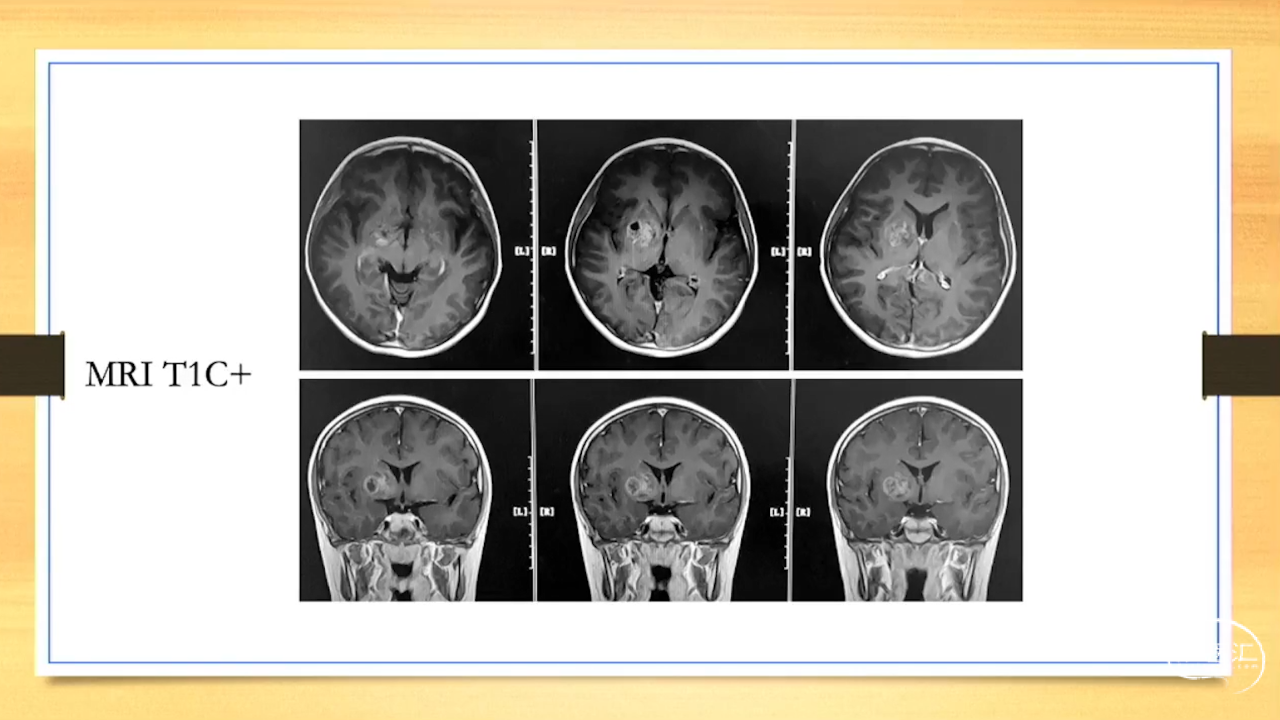

张荣教授:儿童颅内生殖细胞瘤的手术治疗

颅内生殖细胞肿瘤的治疗是手术、放疗、化疗、内分泌及其他多学科的整合治疗。及时、精准、合理的手术治疗是iGCT患者提高生存率、降低并发症、改善神经内分泌功能的关键。